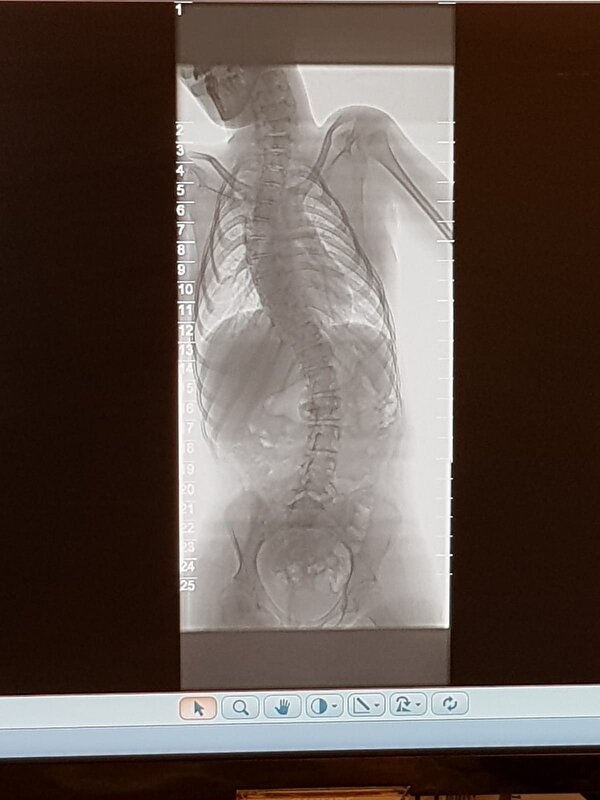

Hopelijk herstelt ze goed van haar zware operatie! Hoe lang gaat ze nog in het ziekenhuis liggen? Dan weet ik ongeveer hoeveel tijd ik nog heb om een kaartje te sturen